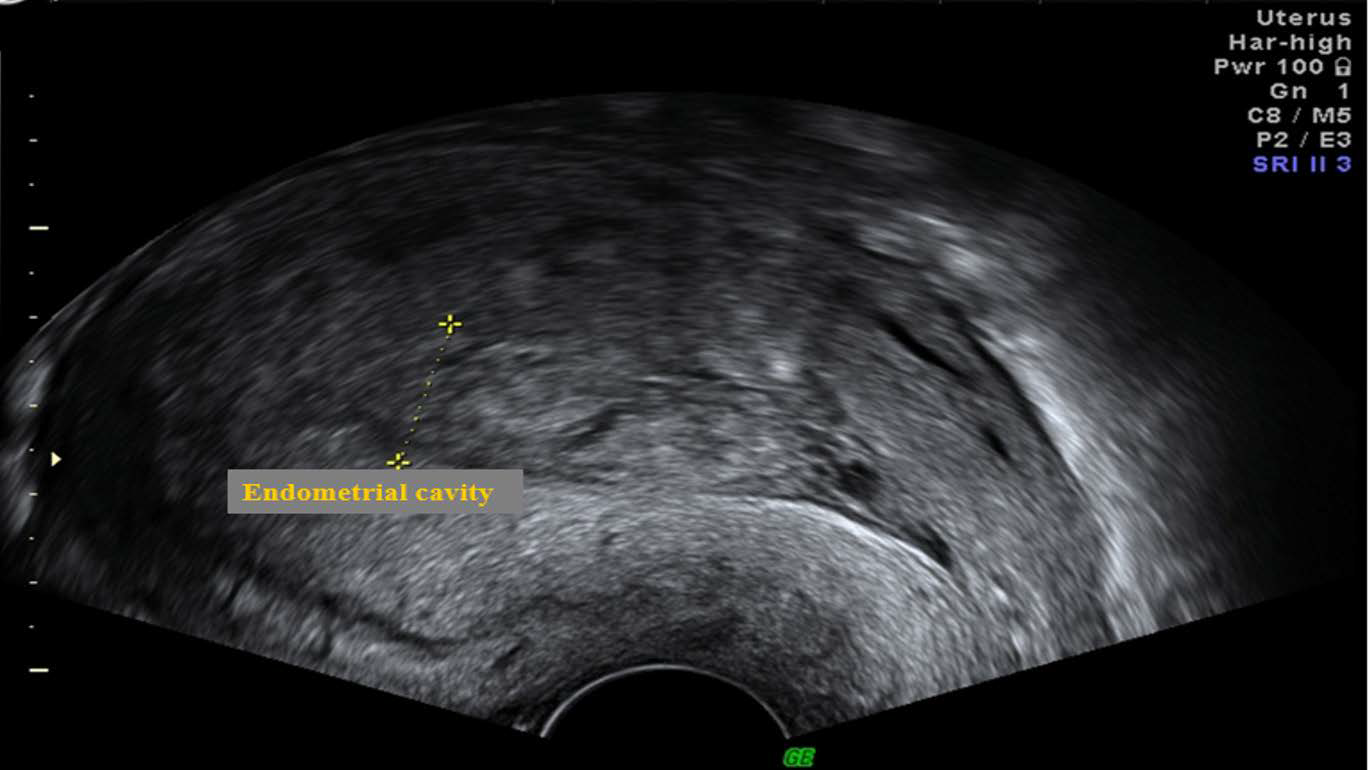

Figure 2: Echogenic debris within the endometrial cavity seen in the sagittal plane on transvaginal scan 12 hours post vaginal delivery.

figure 2